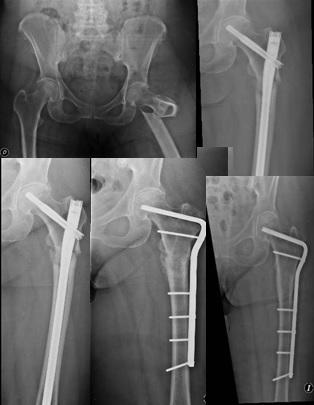

Si bien es cierto que no existen todavía estudios controlados que determinen el tipo de tratamiento quirúrgico para las fracturas, un reciente estudio de revisión39 sugiere que, en los casos de fractura atípica completa subtrocantérica o diafisaria femoral, y debido a que los bifosfonatos inhiben la remodelación osteoclástica, se recurra a un tratamiento que favorezca la curación por reparación encondral. Por ello, se recomienda, en este tipo de fracturas, el enclavado endomedular con clavo largo fresado que proteja de una posible nueva fractura de la diáfisis femoral.39 Los dispositivos tipo placa con tornillos deslizantes, al no favorecer la reparación encondral y al tener una alta tasa de fracasos, no estarían recomendados como método de osteosíntesis de este tipo de fracturas. En nuestra serie, utilizamos un clavo cefalomedular para todas las pacientes y tan solo en dos efectuamos una revisión quirúrgica, en la cual se escogió una placa de ángulo fijo como implante (Figura 2), con buenos resultados, y en el grupo de pacientes con fracturas subtrocantéricas sin asociación con bifosfonato, se efectuó la revisión con una artroplastia parcial de cadera. En la bibliografía, se han publicado casos de seudoartrosis en fracturas tratadas tanto con placas con tornillos deslizantes, como con clavos cefalomedulares. Nuestra experiencia nos revela que, para fracturas subtrocantéricas de trazo transversal u oblicuo corto, el enclavado endomedular es un diseño que otorga ventajas biomecánicas, manteniendo la biología del hematoma fracturario y, sumado a ello, permite una rehabilitación con carga precoz según tolerancia.

Figura 2.

Revisión de una fractura asociada al tratamiento con ibandronato, con clavo de ángulo fijo y curación.